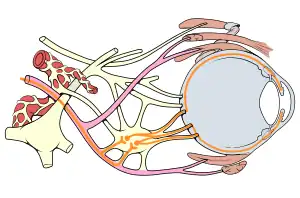

| Eye nerves diagram | |

Mechanism

As the pair of oculomotor nerves arises from different subnuclei in the midbrain, courses through different structures in the brain and branches into superior and inferior divisions after exiting the cavernous sinuses, any lesions along its path will produce different pathological features of the third nerve palsy. The parasympathetic aspect of the nerve (which constricts pupils and thicken the lens) is located on the nerve surface, supplied by pial blood vessels. The nerve's core contains the main trunk of the oculomotor nerve, supplied by vasa vasorum. Thus pathologies affecting the nerve's core without affecting the superficial part of the nerve (thus sparing the pupillary reflex) are known as "medical" oculomotor nerve palsy. The "surgical" type of oculomotor nerve palsy is caused by external structures compressing on the nerve or trauma, which affects the entire nerve, thus affecting pupillary reflex.[2]

Ischemic stroke selectively affects somatic fibers over parasympathetic fibers, while traumatic stroke affects both types more equally. Ischemic stroke affects the vasoneurium, which starts to supply the nerve from outside to inside. As the somatic fibers are located in the inner part of the nerve, these fibres are affected more in the setting of ischemia. A similar mechanism is also accurate for diabetes. Therefore, while almost all forms cause ptosis and impaired movement of the eye, pupillary abnormalities are more commonly associated with trauma and the "surgical third" rather than with ischemia (the "medical third"). A posterior communicating artery aneurysm will generally cause compression of the entire third nerve and will this prevent any nerve signal conduction, affecting the somatic system as well as the autonomic. The compression of the external autonomic fibres renders the pupil nonreactive and leads to the "surgical third" nerve palsy.

Oculomotor palsy can be of acute onset over hours with symptoms of headache when associated with diabetes mellitus. Diabetic neuropathy of the oculomotor nerve in a majority of cases does not affect the pupil.[3] The sparing of the pupil is thought to be associated with the microfasciculation of the fibers that control the pupillomotor function located on the outmost aspect of the occulomotor nerve fibres; these fibres are spared because they are outermost and therefore less prone to ischemic damage than are the innermost fibres.[4]